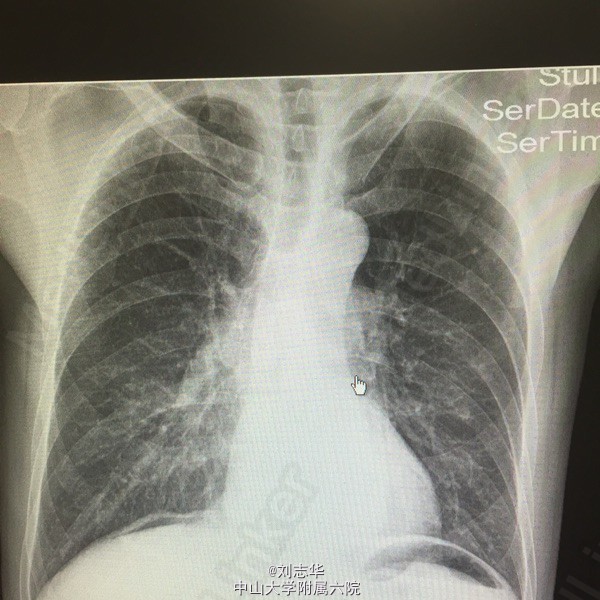

患者男,64岁,两年前于外院因"胃溃疡穿孔"行"胃大部切除术"。一天前无明显诱因出现上腹疼痛,程度剧烈,刀割样,急诊行腹平片检查:双膈下游离气体。

查体:上腹部10cm手术疤痕,全腹压痛反跳痛明显。肠鸣音1-2次/分。余无特殊。 腹平片:双膈下游离气体。